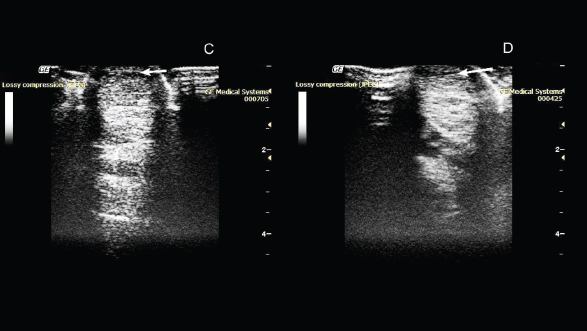

Fig. 2. Ultrasonography of the superficial digital flexor. (C): 50th day after the introduction of plasmid DNA. (D): 80th day after the introduction of plasmid DNA.

On the 50th day after administration of the drug, the absence of lameness was noted during the examination. Ultrasound examination showed a decrease in the hypoechoic zone, and an increase in echogenicity at the site of damage was also observed (Fig. 2).

On the 80th day, the absence of lameness was still observed. Ultrasound examination showed a decrease in the hypoechoic zone and an increase in echogenicity at the site of injury. This indicated the presence of a reparative process. As the clinical and ultrasound characteristics of the damaged tendon improved, a gradual introduction of trotting was prescribed in addition to walking.